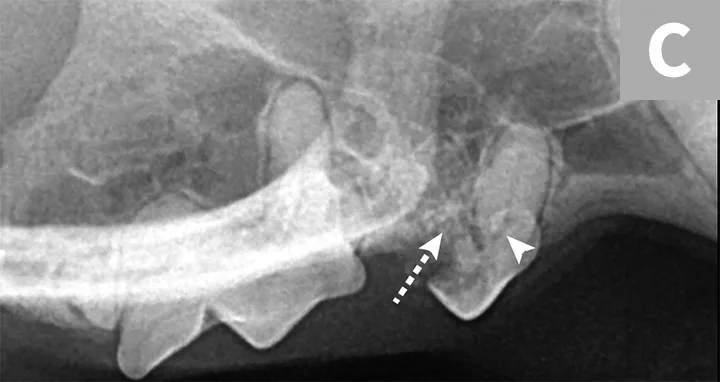

Tooth resorption type is determined via intraoral radiography based on root opacity and periodontal ligament space (see Types of Tooth Resorption Based on Radiographic Appearance and Figure 2).

Radiograph of a left mandibular molar tooth in a cat with Type 1 resorption (A) in which focal or multifocal radiolucency can be seen with otherwise normal radiopacity and normal periodontal ligament space. Radiograph of mandibular incisors and canine teeth in a cat with Type 2 resorption (B; white arrow) in which narrowing or disappearance of periodontal ligament space is present in at least some areas, and part of the tooth demonstrates decreased radiopacity. Radiograph of the right maxillary third and fourth premolars in a cat with Type 3 resorption (C); the third premolar features Type 1 resorption of the mesial root (arrowhead) and Type 2 resorption of the distal root (dashed arrow) with exposure to the oral cavity.